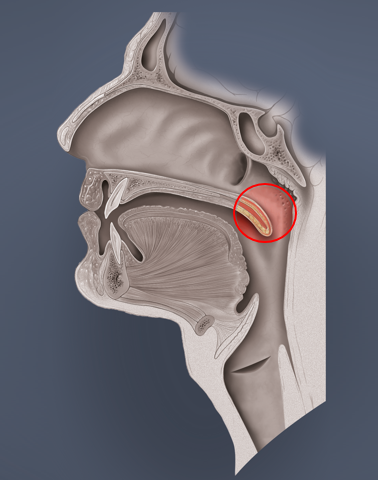

- Eustach’sche Röhre (Tuba auditiva, engl. Eustachian tube)

Die Tube ist eine 30 – 35 mm lange, mit Flimmerepithel ausgekleidete, Röhre, die das Mittelohr und den Nasenrachenraum verbindet. Ohne eine ausreichende Belüftungsfunktion ist der Druckausgleich unmöglich, da dies der einzige Zugang zum Mittelohr ist. Im Normalzustand ist die Tube geschlossen, öffnet sich jedoch beim Schlucken, Gähnen oder bestimmten Lauten und natürlich beim Druckausgleich.

Die Valsalva-Technik

Antonio Maria Valsalva war ein italienischer HNO-Arzt (1666 – 1723). Die nach ihm benannte Technik sollte bei Mittelohrentzündungen die Belüftung und den Abtransport des Eiters oder Schleims aus dem Mittelohr durch die Tube begünstigen. Dabei bediente er sich der Bauchpresse, d. h. Anspannung der Bauchmuskulatur. Die Valsalva-Technik basiert ergo auf recht hohem Druck und verringert das Lungenvolumen. Die Mundhöhle wird mit dem T-, Ca- oder H-Lock verschlossen (s. o.). Dieser hohe Druck ist medizinisch nicht immer erwünscht. Wenn beispielsweise ein PFO (persistierendes Foramen ovale) vorliegt, können dadurch Mikroblasen von der rechten Herzhälfte in die arterielle linke Herzhälfte gedrückt werden und so das Risiko für eine Dekompressionserkrankung erhöhen. Zudem kann bei zu forcierten Versuchen mit der kraftvollen Bauchmuskulatur ein Ödem zum Flimmerepithel der Tube „hingedrückt“ werden. Danach ist der Druckausgleich dann nur noch schwer möglich. Bei zu hohem Druckgradienten legen sich zudem die Wände der Tube aneinander und eine Öffnung ist nicht mehr oder nur sehr erschwert möglich.

Die Frenzel-Technik

Der deutsche Luftwaffenarzt Walter Gotthold Frenzel entwickelt diese Technik für den Druckanstieg in Kampffliegern bei schneller Höhenabnahme. Diese Technik basiert auf „mechanischem Druck“, da hierbei die Luft im Mundraum durch die Zunge Richtung hinten oben in den Nasenraum gedrückt wird. Dabei kann die Zunge in der T-, Ca- oder H- Stellung sein. Die Frenzel-Technik ist eine sanfte Methode um den Druckausgleich zu bewältigen, da weniger Druck aufgebaut wird. Manchen Tauchern fällt es dadurch leichter die Tube zu öffnen. Das Risiko eines Shunts von Mikroblasen, bei vorliegendem PFO, auszulösen ist geringer als beim Valsalva-Manöver. Die Frenzel-Technik stellt jedoch keinen Schutz davor dar!

Sowohl beim Valsalva- als auch beim Frenzel-Manöver muss der weiche Gaumen natürlich offen sein und den Weg zum Nasenraum freigeben. Beim Valsalva ist die Stimmritze offen, beim Frenzel geschlossen (s. Bilder oben).

Da hierbei die beiden kleinen Muskeln (Tensor und Levator veli palatini) stark involviert sind, machen wir uns zunächst die anatomische Lage dieser Muskeln klar. Der Musculus levator veli palatini kommt vom Felsenbein (der Knochen hinter dem Ohr) und setzt am weichen Gaumen an, den er bei Anspannung nach hinten oben bewegt. Dabei nimmt er den Eingang der Tube mit, der sich dabei öffnet. Der Musculus tensor levi palatini kommt auch von einem Schädelknochen, dem sogenannten Keilbein und setzt am weichen Gaumen an. Wenn er in Aktion tritt, spannt er den weichen Gaumen an und versteift dabei die vordere seitliche Wand der Tube, die dadurch in geöffnetem Zustand bleibt.

Zu 1.) False

Der „False“ (= falsche) Hands-Free-Druckausgleich wird ähnlich wie der Frenzel durch die Zunge durchgeführt. Die Nase ist dabei lediglich durch die sehr festsitzende Maske verschlossen. Die Luft wird durch die in T-Stellung befindliche Zunge langsam nach hinten oben „gestempelt“. Durch das abnehmende Volumen im Mundraum steigt der Druck und die Luft entweicht über den Nasenraum Richtung Tube. Im Zusammenspiel mit den beiden kleinen Muskeln (Musculi tensor und levator veli palatini) öffnet sich die Tube und der Druckausgleich im Mittelohr kann stattfinden. Bei offenem weichen Gaumen ist die Glottis hierbei verschlossen.

Zu 2.) Toynbee

Diese Technik wurde nach dem britischen HNO-Arzt Joseph Toynbee benannt (1815 – 1866). Er fand heraus, dass die Muskeln tensor und levator veli palatini beim Schluckakt die Tube öffnen. Bei manchen Tauchern gelingt er Druckausgleich rein durch Schlucken.

Zu 3.) Pure

Mit ein bisschen Übung kann man lernen die für die Tubenöffnung verantwortlichen Muskeln bewusst anzusteuern. Das kann man durch willentliche Anspannung der Muskulatur um das Kiefergelenk und des weichen Gaumens ausprobieren. Ihr könnt auch die Kehlkopfmuskeln zu Hilfe nehmen. Das muss man ausprobieren. Bei erfolgreicher Anspannung unserer zwei kleinen Tuben-Hilfsmuskeln spürt ihr eine Druckveränderung im Mittelohr und wisst, dass es funktioniert hat.